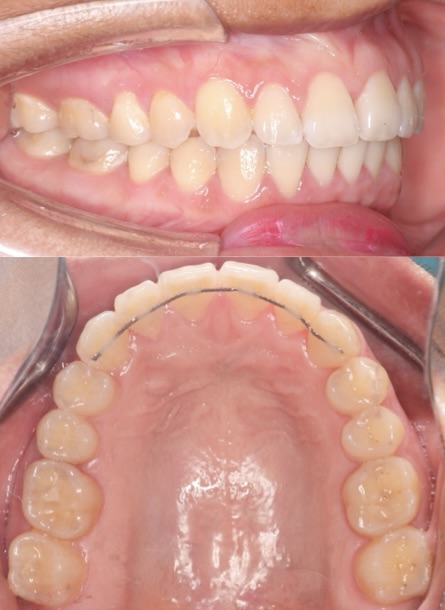

Before

After

BRACES - SPACE CLOSING

This patient presented with generalized spacing and misaligned teeth. Through comprehensive orthodontic treatment using braces, we successfully closed all spaces and aligned the teeth into an ideal arch form. A fixed lower retainer was placed to maintain long-term stability. The result is a healthier, more confident smile with improved function and aesthetics.